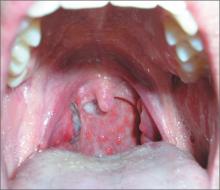

Dark area on tonsil

A 27-year-old man sought care for a severe sore throat and fever that he’d had for 2 days. He was also worried about the dark area on his right tonsil. He denied rhinorrhea and cough. He had a history of allergic rhinitis. On physical exam, the patient had a temperature of 101°F, a dark necrotic area on his right tonsil, and posterior lymphoid hyperplasia (cobblestoning). He also had tender anterior cervical adenopathy.

The FP explained that the dark area on the tonsil was secondary to infection and would resolve over time. He also told the patient that the cobblestone pattern on the posterior pharynx may have been secondary to a history of allergic rhinitis or could have been newly acquired as part of the strep pharyngitis.

Posterior lymphoid hyperplasia is not a specific finding, even though it is commonly seen in allergic rhinitis and viral pharyngitis. Note, too, that patients may have strep pharyngitis even without tonsillar exudate.